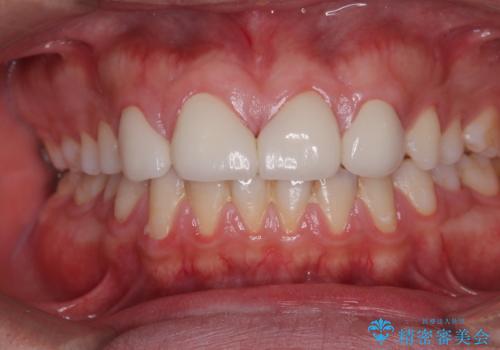

欠損して隙間のある前歯 オールセラミッククラウンで自然な口元に

ひとつひとつの歯の幅は非常に大きくなりましたが、手っ取り早く隙間が改善されたとのことで、大変満足していらっしゃいました。